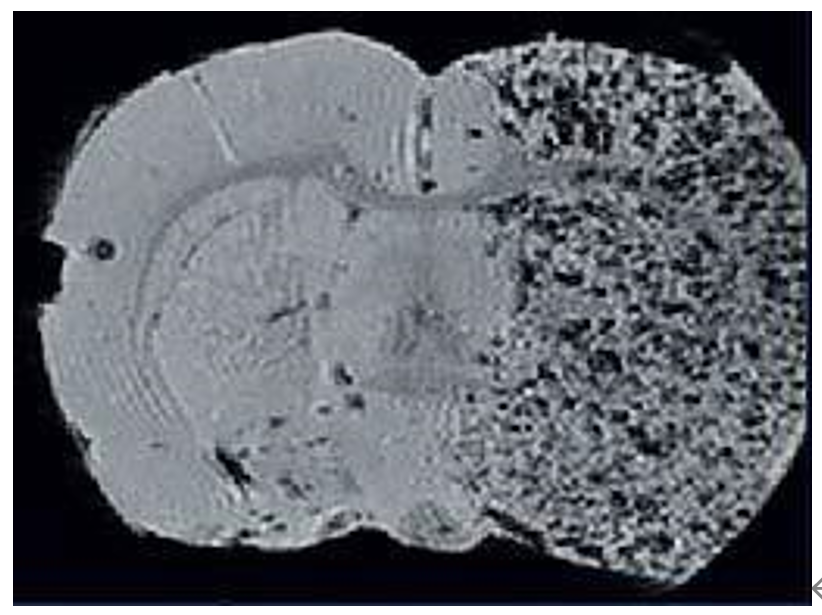

3、Cellular Imaging

Mesenchymal stem cells were labeled and used as markers for stroke regions. They are readily visible in T2- and T2*-weighted images both in vivo and ex vivo. Full 3D brain coverage enables quantification and volume rendering.